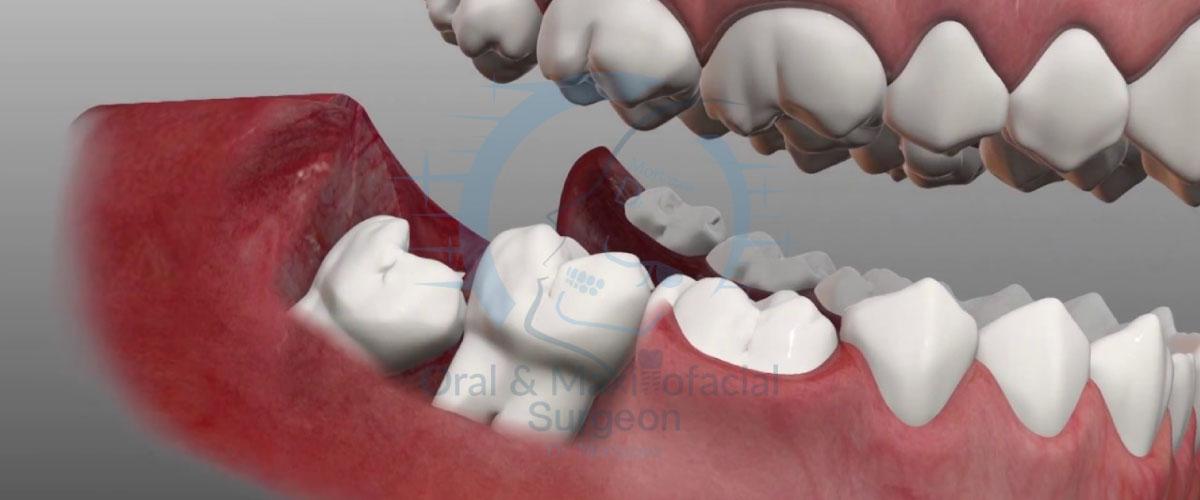

- نهفتگی افقی (Horizontal Impaction): این نوع نهفتگی یکی از خطرناکترین انواع است. دندان عقل به صورت کامل به پهلو خوابیده و به ریشه دندان مولر دوم فشار میآورد. این فشار میتواند باعث تخریب ریشه و پوسیدگی دندان مجاور شود.

- نهفتگی زاویهدار (Angled/Mesial Impaction): در این حالت، دندان عقل با زاویه به سمت دندان مجاور رشد میکند و به آن فشار وارد میکند. این شایعترین نوع نهفتگی است.

- آسیب به دندانهای مجاور: فشار ناشی از دندان عقل نهفته یا کج میتواند به ریشه دندان مولر دوم فشار وارد کرده و باعث پوسیدگی، آسیب به مینای دندان یا حتی تحلیل رفتن ریشه آن شود. این آسیبها اغلب در عکسهای رادیوگرافی مشخص میشوند.